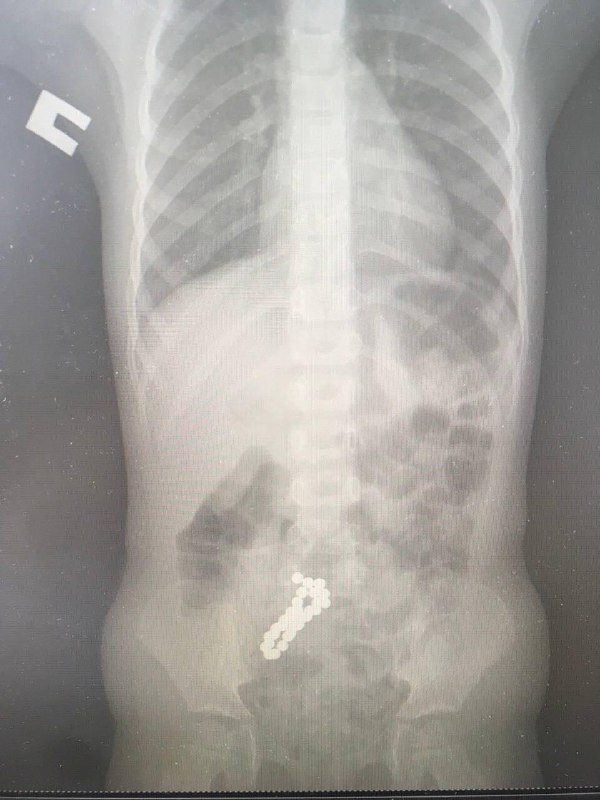

🩺 Из кишечника 4-летней девочки извлекли 30 магнитов Родители рассказали медикам, что дома пропал неокуб - магнитный конструктор из блестящих сфер. Проведенные исследования подтвердили, что его элем